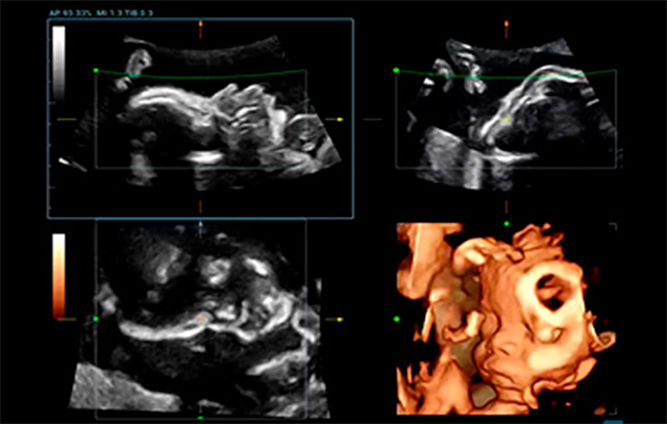

Smart Face